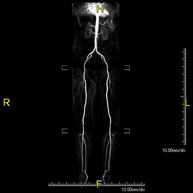

Angio-RM Arterial d'extremitats inferiors

Angio-RM Arterial d'extremitats inferiorsProva diagnòstica no invasiva que consisteix en l'estudi de l'artèria aorta abdominal per obtenir imatges d'alta definició anatòmica mitjançant l'ús d'un camp electromagnètic i ones de ràdio (amb un emissor i un receptor). És indispensable l'ús de contrast intravenós paramagnètic (Gadolini). No obstant, no utilitza radiació ionitzant. La qualitat de les imatges permet realitzar reconstruccions en 2D i 3D. Està especialment indicada en pacients amb sospita de malaltia vascular de les dues extremitats, en pacients amb malaltia vascular de les dues extremitats com a mapa vascular abans del tractament (percutani o quirúrgic), com a mapa vascular prequirúrgic en pacients amb lesions òssies o musculars que requereixin cirurgia, etc.